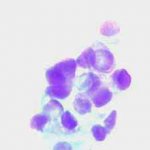

Κατόπιν αυτού, παρακέντηση λεπτής βελόνης κάτω από υπερηχογραφικό έλεγχο και άμεση χρώση παρασκευάσματος κατά Papanicolaou. Κυτταρολογικώς χαρακτηριστικές εικόνες νεοπλασίας.